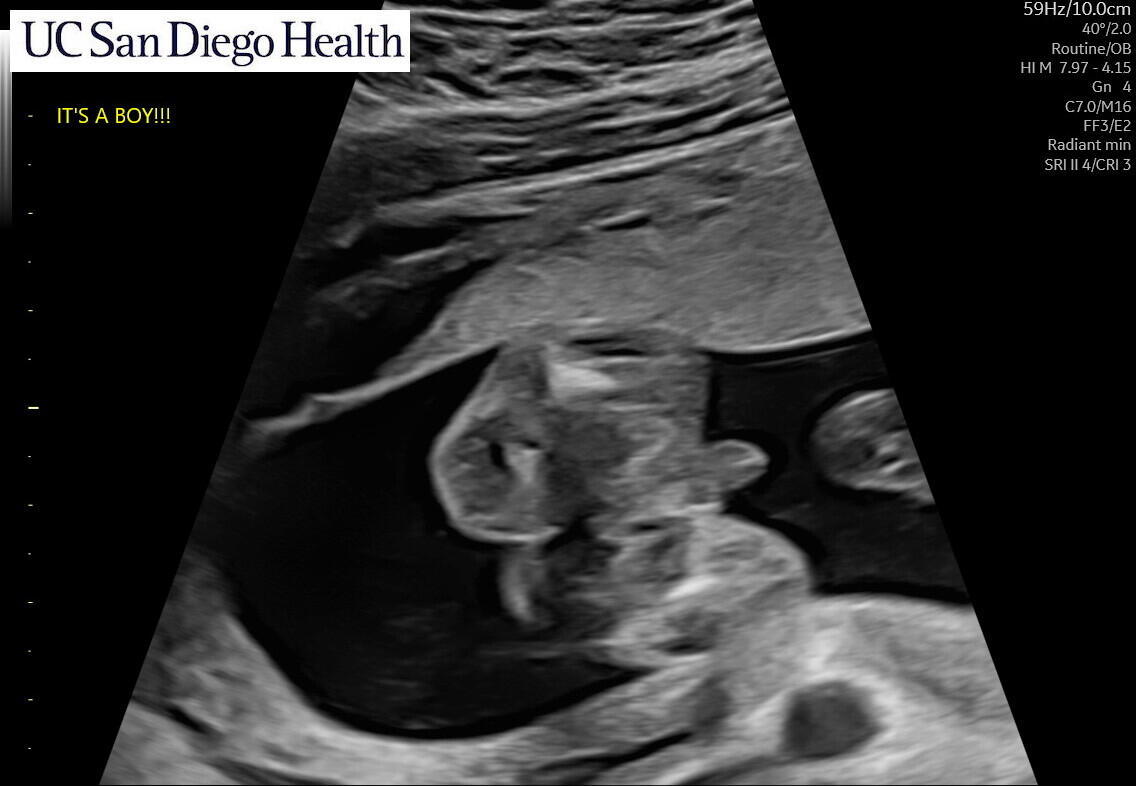

Coming March 2025!

We’re thrilled to be welcoming our baby boy in late March 2025! We’re planning a baby shower in January, we'll see you there!